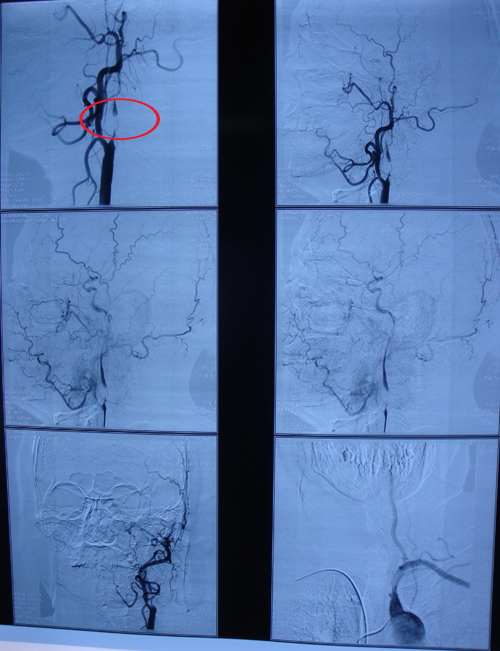

颈动脉超声:双侧颈动脉内膜增厚;左侧颈内动脉球部斑块形成延伸至颈内动脉近段局部狭窄(约90-99%),左侧颈总动脉阻力增高;右侧颈内动脉球部斑块形成延伸至颈内动脉近段局部管腔(约50-69%);右侧椎动脉颅外段血流阻力增高。

该患者为典型的TIA发作,且左侧为责任病变,右侧肢体症状,高龄,有高血压病史,符合颈动脉内膜剥脱术手术指征。手术后可获得明显改善,避免卒中发作。2010年9月4日,由协作组张勤奕教授和宁新宇教授顺利为其实施了左侧颈内动脉内膜剥脱术。目前该患者症状已获得明显改善。